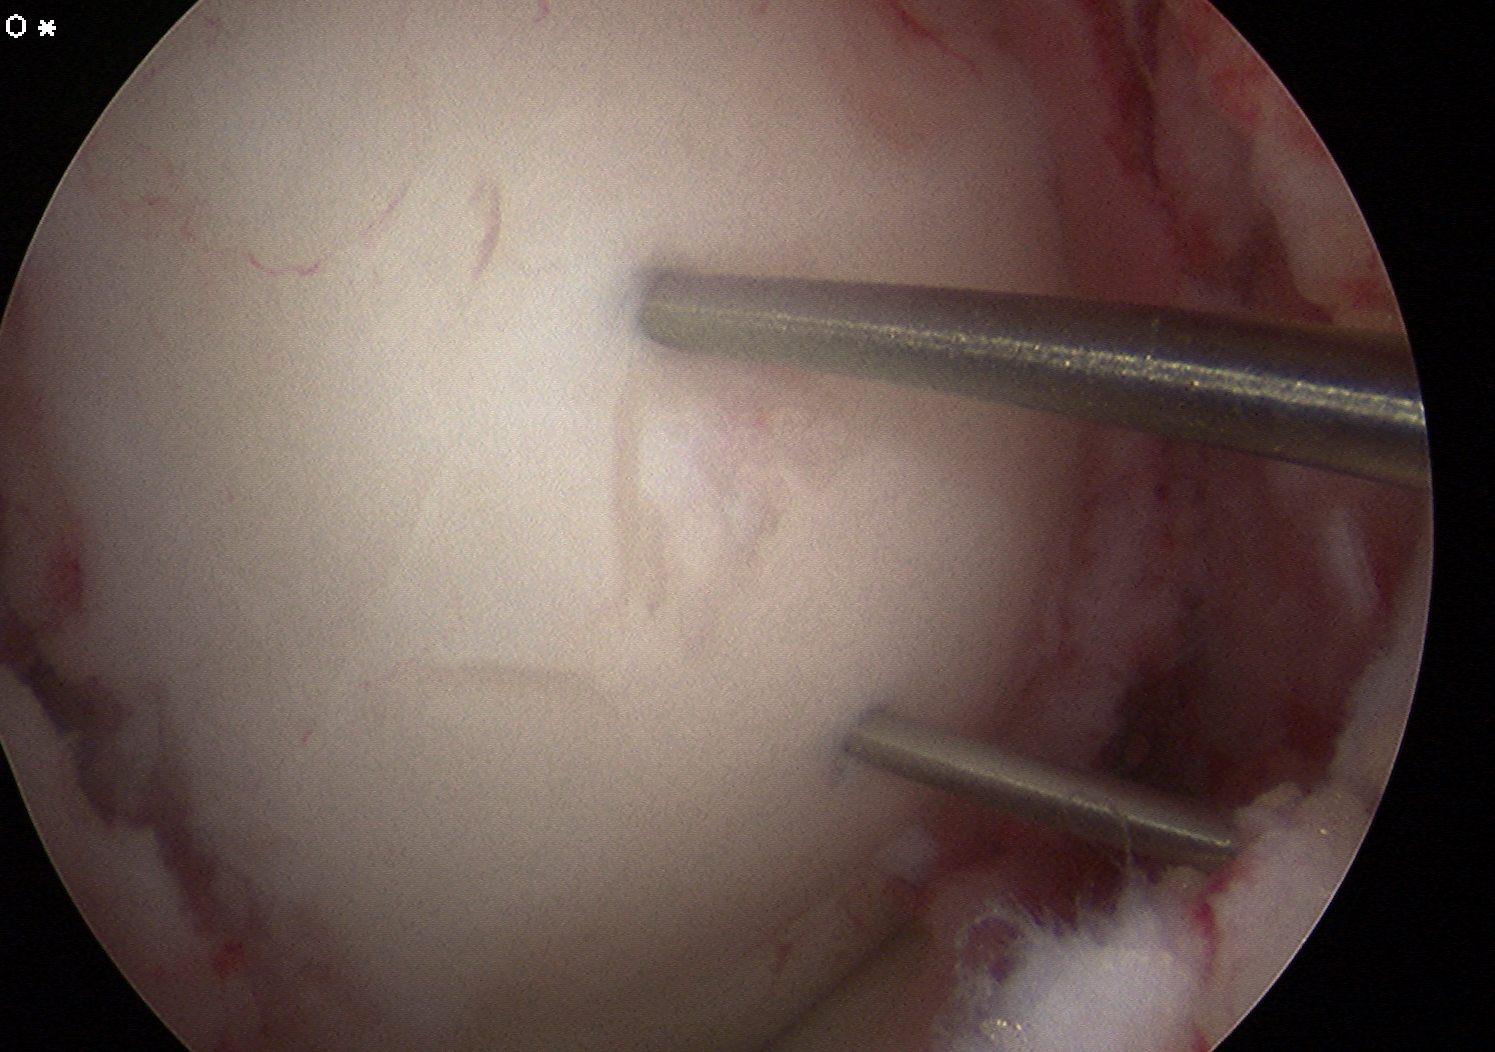

- immediately reduce fragment

- secure with K wires for cannulated screws

ORIF

In this case, 2 x Arthrex bioabsorble screws used

- drill and tap over wire

- remove wire

- insert screw and bury head